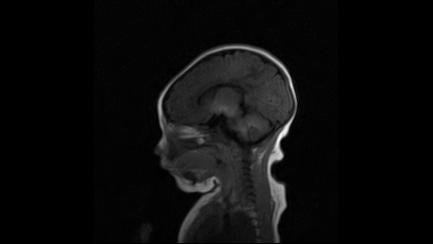

标题: PED3413:患儿女6天体检

缺血缺氧性脑病

6天为新生儿,髓鞘发育正常;左侧颞顶叶蛛网膜下腔增宽,请结合临床。

1。缺血缺氧性脑病2。左侧颞顶叶外部性脑积水,可观察

半卵圆中心上方层上可见对和乐大脑皮质t1高信号,考虑有hie可能,不知有何症状,建议加做dwi及复查

符合缺氧缺血性脑病影像表现。